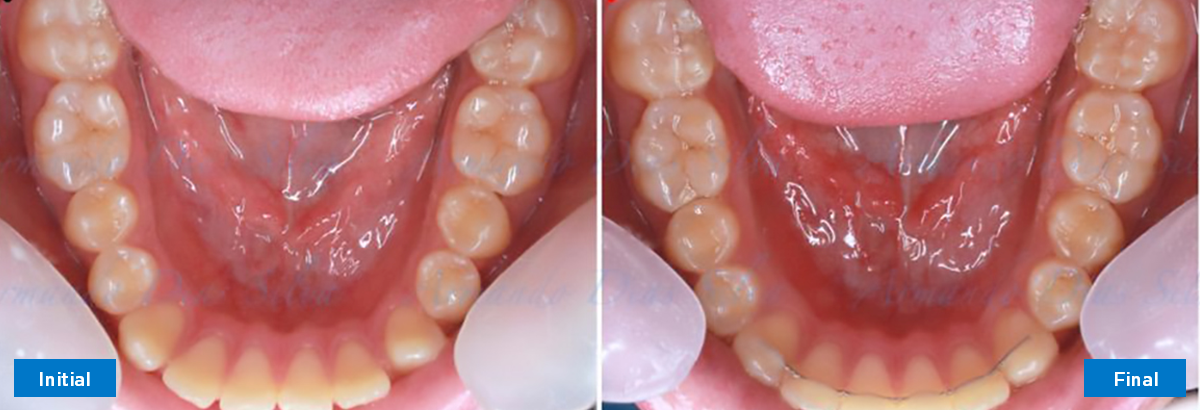

Clase II, Div. 1: Protrusión del incisivo central y espacios anteriores (SureSmile® Aligners)

Principal queja del paciente: Protrusión del incisivo central y mordida abierta. El paciente rechaza la expansión del arco palatino (MARPE) y las extracciones.

Este paciente adolescente presenta molares de Clase II y no le gusta su mordida abierta ni lo protrusivos que son sus dientes frontales. Por sus fotografías faciales, parece que su mandíbula es retrognática o le falta volumen en la barbilla. El historial del paciente también indica que existe un problema funcional al no haber guía de los incisivos.

• Espaciamiento leve de las arcadas superior e inferior (deficiencia transversal de 3,45 mm)

• Deficiencia transversal maxilar leve (3,45 mm)

• Incisivos superiores e inferiores proclinados

• Molares de clase I logrados con distalización y sin elásticos

• Sin expansión maxilar, respetando la envoltura periodontal

• Incisivos inferiores retroinclinados, que mejoran la estabilidad a largo plazo